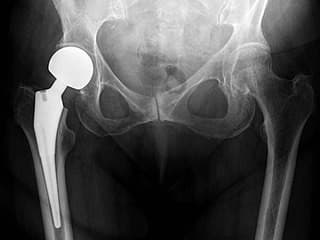

Total Hip Arthroplasty – үеийг бүтэн солих мэс засал

Хугарал засах мэс засал image9

УНТЭ-т хийгдсэн мэс заслын зураг

Periprosthetic fracture-Хиймэл үе суулгасны дараах хугарал

Хугарал засах мэс засал image10Хугарал засах мэс засал image11

Өвчтөн Б 52 настаЙ эмэгтэй 2020 оны 04 сард дунд чөмөгний хүзүүний эмгэг хугаралын улмаас түнхний үеийг бүтэн солих мэс засал хийлгэсэн. Мэс заслын дараах 25 дах хоног дээр явганаас халтирч унаж дахин хугаралыг зассан үеийн рентген зураг